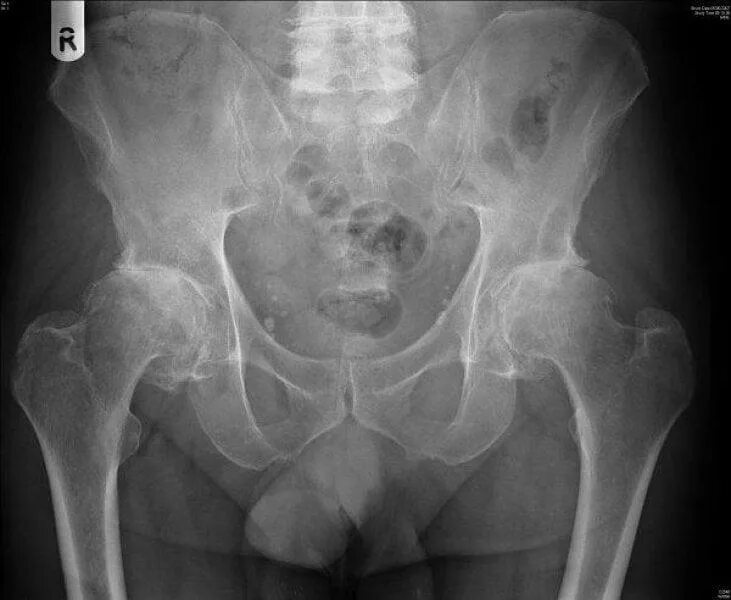

Артроз тазобедренных суставов 1 стадии